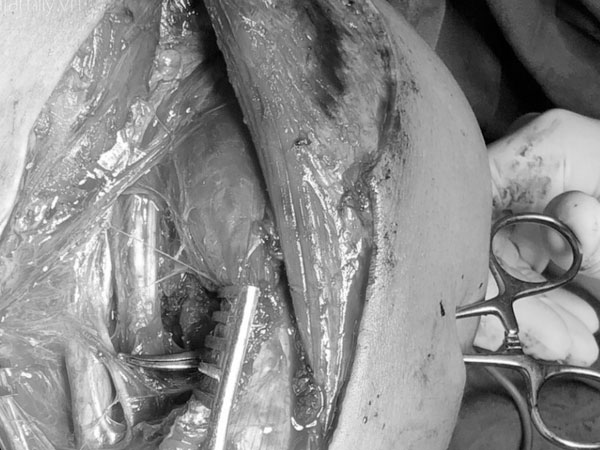

Bác sĩ Phạm Đình Vinh, Khoa Chấn thương chỉnh hình, bệnh viện Hoàn Mỹ ITO Đồng Nai thông tin, qua thám sát vết thương, phát hiện dây thần kinh quay và thần kinh cơ bì cánh tay trái của bệnh nhân bị đứt hoàn toàn.

Nghi ngờ vết thương đã làm tổn thương đến thần kinh, kíp trực tiến hành các xét nghiệm thăm dò. Kết quả điện cơ cho thấy, bệnh nhân bị tổn thương sợi trục dây thần kinh quay và thần kinh bì cánh tay.

Xác định tình hình vết thương, A. được các bác sĩ chuyển sang phẫu thuật vi phẫu nối lại các dây thần kinh vận động bị cắt đứt.

Bệnh nhân đã được các bác sĩ áp dụng kỹ thuật vi phẫu để khâu nối thành công 2 dây thần kinh trong 3 giờ liền.

"Vi phẫu thuật là những phẫu thuật phải sử dụng đến kính hiển vi với để xử lí phẫu tích, khâu nối những mạch máu, thần kinh có kích thước chỉ khoảng 1mm, đường kính tương đương 1/10 đường kính của sợi tóc.

Phương pháp này được ứng dụng nhiều trong phẫu thuật nối lại mạch máu và bộ phận cơ thể đứt rời (như bàn tay, ngón tay, chân, môi mũi, tai, dương vật…), tạo hình che phủ bằng các vạt tự do, ghép tạng…

Việc áp dụng kỹ thuật vi phẫu đã giúp ích rất nhiều cho những bệnh nhân bị tổn thương, phục hồi được cảm giác, vận động, hòa nhập với cuộc sống đời thường" - bác sĩ chia sẻ.